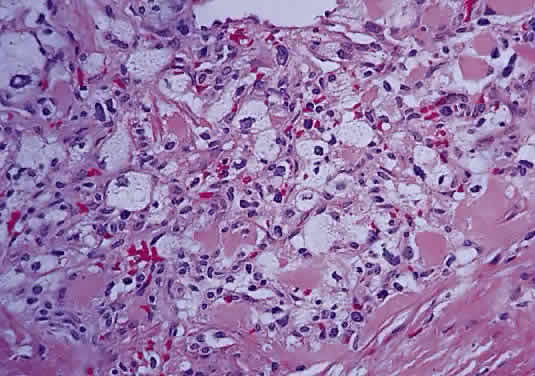

Intraoperatively, hemangioblastoma appears as a reddish, circumscribed tumor that typically is well demarcated from the nerve, although often the central portion is involved. Microscopically, the most striking feature is the abundance of vascular channels, most of which have the appearance of capillaries. Reticulin-staining highlights the vascular network. Between them are stromal cells containing abundant vacuolated cytoplasm, which is due to the presence of lipid. Although bland, the nuclei of the stromal cells are variable in appearance and may exhibit focal marked hyperchromasia (Figs. 46 and 47). Electron microscopy shows that the large stromal cells contain intracytoplasmic particles of lipid and glycogen. Scattered foci of extramedullary hematopoiesis may be present as a consequence of erythropoietin production by the tumor cells. Mast cells also are often readily identifiable. Small cysts are frequent, and the cyst wall consists of gliosis, in which may be found numerous Rosenthal fibers.

Fig. 46. Hemangioblastoma of optic nerve. Multiple capillary vessels are separated by foamy cells (hematoxylin and eosin staining).

Fig. 47. Hemangioblastoma of optic nerve. Foamy cells are a prominent feature between the thin-walled capillary vessels (hematoxylin and eosin staining).